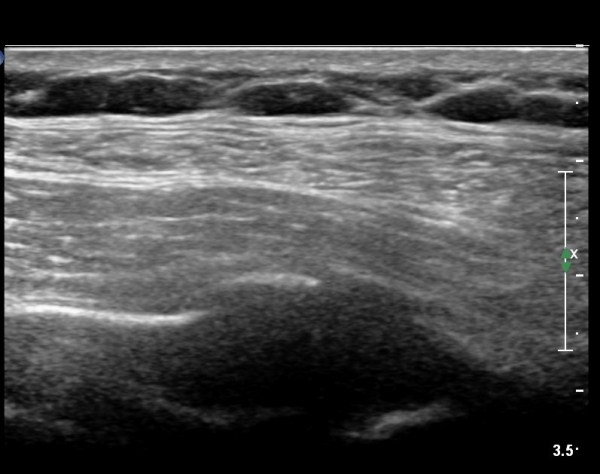

lin longitudinal scan of 7th. rib, appearance of bony mass(protrusion) just like callus(image 1).

on moving of prove a little, there is bony protrusion(osteoblastic lesion) and hypoechoic(osteolytic)  lesion(image 2, 3, 4).

in transverse scan, visualization of osteoblastic mass with central osteolytic lesion(image 5, 6).

As like this case, visualization of osteoblastic lesion and osteolytic lesion in simultaneously  suggests a malignant mass.